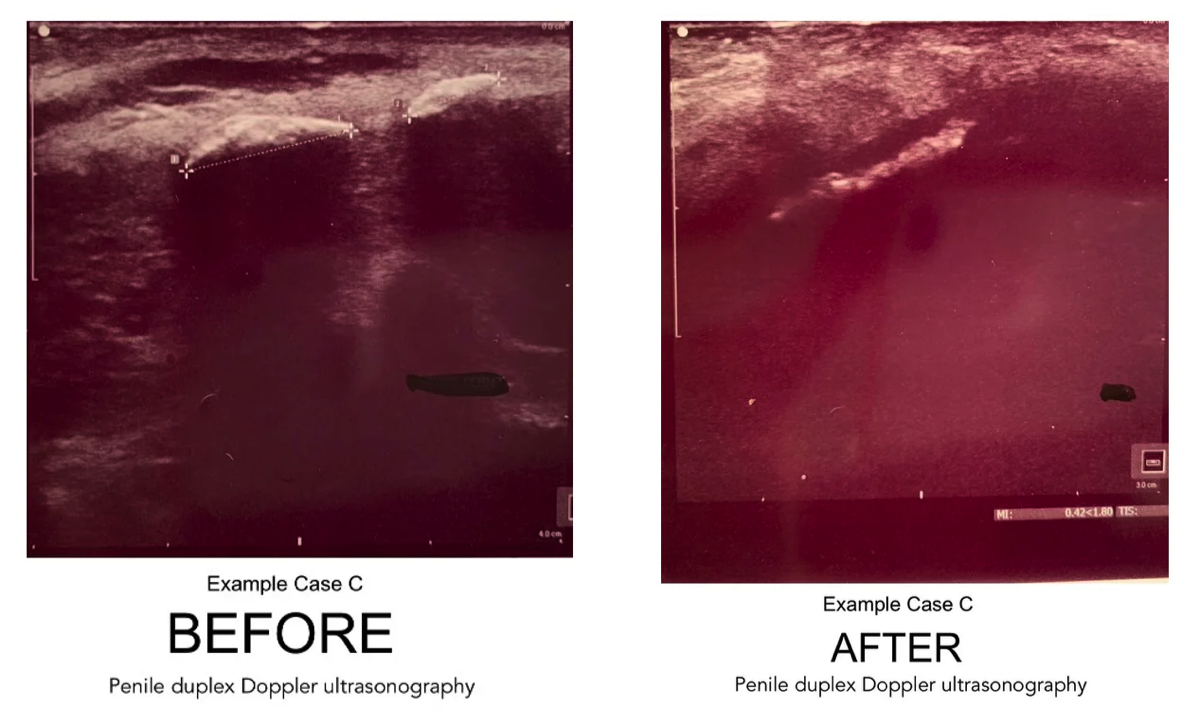

Calcified Plaque: Before & After Sonogram Images

Following are examples of "before and after" duplex sonogram images of ExoSurge® Peyronie's patients with calcified plaques. The reduction of calcified plaques is readily apparent, even to an inexperienced layperson. As far as we are aware, these photos are the first sonographic evidence of a visible reduction in calcified Peyronie's plaque from conservative therapy in the history of urology.

A database search using The Clinic’s Electronic Health Records (EHR) system was completed extrapolating patient medical charts with the diagnosis of PD and undergoing treatment between the dates of January 1, 2018, and March 6, 2020. Patient charts were included when they were found to have identifiable and measurable plaque with no less than two duplex doppler ultrasound diagnostic tests within that timeframe providing a pre-treatment ultrasound and a post or intra-treatment ultrasound for comparison. Of these patients, 101 were found to be consistent in receiving treatments during this timeframe. Those excluded were patients who had not been seen in the clinic within three months or more prior to the post or intra-treatment ultrasound tests and considered inconsistent with treatment.

Upon further review it was determined that within this patient sampling of 101, some pre-treatment recordings of the duplex doppler ultrasound diagnostic test was not complete and/or not comparable in recording to the post and/or intra-treatment ultrasound and therefor were not considered a good comparison. These patient charts were removed from the study leaving a total of 70 patient charts for comparison. All duplex doppler ultrasound diagnostic testing during the listed dates was completed by an independent, outside source on site at The Clinic.

Data retrieved from each duplex doppler ultrasound included degree of curve, identification of venous leak, identification of arterial insufficiency, erection grade, size of plaque, and consistency of plaque as either calcified or non-calcified.

A beginning baseline duplex doppler ultrasound analysis that included up to three measurable pieces of plaque was compared to a follow up duplex doppler ultrasound for measurable changes. Data retrieved from both the initial and final duplex doppler ultrasounds included findings of plaque. Plaque size was recorded in a 3-dimensional format in millimeters. Consistency of plaque was recorded as calcified or non-calcified. Penile curvature was identified in degree of curvature, which was then divided into two classes: curvature greater than or equal to 30 degrees and a curvature less than 30 degrees.

For the baseline duplex Doppler ultrasonography, the total number of pieces counted in plaque area Number Two were 42 with the follow up study showing a total of 40. Of the original 42 pieces, 28 were non-calcified and 14 were calcified. On the follow up duplex Doppler ultrasonography analysis for plaque in Area Two, 32 were non-calcified and 8 were calcified, a 43% decrease in calcified plaque.

The average total size as measured from the baseline duplex Doppler for area two was 209.9 mm3 and the follow up results measured 63.4 mm3, representing a 70% reduction in penile plaque.